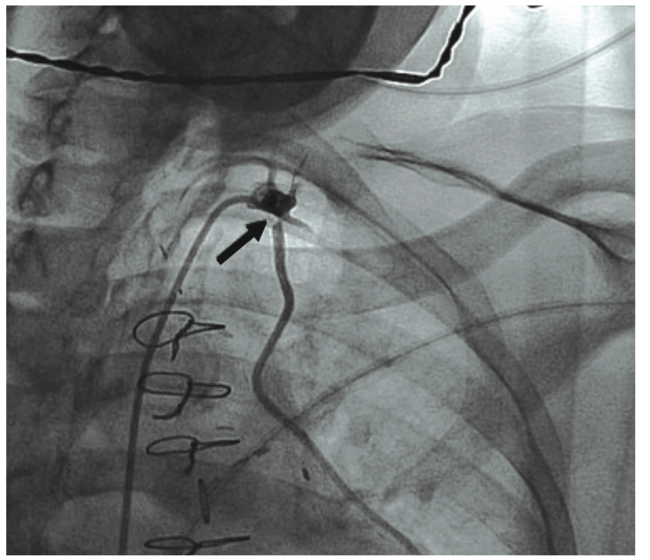

There was also mild to moderate non-obstructive disease of the SVG to the right PDA. The ostial LIMA lesion was validated with the administration of intracoronary nitroglycerin and later with intravascular ultrasound (IVUS) (Figure 1B), as well as by the observation of severe balloon compression during the interventional procedure, as described below.

Given the patient’s complex anatomy with suboptimal hemodynamics, ad hoc percutaneous coronary intervention (PCI) was deferred in lieu of further heart team discussion and medical optimization. Her antiplatelet regimen was escalated from clopidogrel to ticagrelor, with a loading dose of 180 mg followed by 90 mg twice daily maintenance. She was scheduled for a series of extra hemodialysis/ultrafiltration sessions, leading to eventual percutaneous intervention several days later. Femoral access was employed in both diagnostic and intervention cases, given current and prior bilateral upper arm fistulas. Repeat pre-PCI LVEDP was improved at 23 mmHg. The LIMA to mid LAD ostial 75 to 80% stenosis with moderate to severe calcification was treated successfully with balloon angioplasty and intravascular lithotripsy (IVL) of a 3.5 mm x 12 mm C2 balloon (Shockwave Medical), using 50 pulses. IVL was followed by placement of a Xience Skypoint 3.5 mm x 12 mm drug-eluting stent (DES) (Abbott Vascular) that was post dilated to >3.75 mm at high pressure, resulting in 0% residual stenosis and normal blood flow grade 3 (TIMI [Thrombolysis in Myocardial Infarction]) (Figure 3A, Video 2).

The native proximal left circumflex artery (TIMI-2 flow pre, type C lesion) had diffuse calcification with a 95% stenosis that was treated successfully with a Diamondback 360˚ coronary orbital atherectomy system (CSI), balloon angioplasty, and Shockwave intravascular lithotripsy with a 3.5 mm x 12 mm C2 balloon using 30 pulses, followed by placement of a Resolute Onyx 3.5 x 26 mm DES (Medtronic) extending back into the left main, and post dilated to >4 mm at high pressure, resulting in 0% residual stenosis with TIMI-3 flow. The OM2 had a 100% functionally occluded competitive vein graft with tortuous flow that was treated successfully with orbital atherectomy, balloon angioplasty, and placement of a Resolute Onyx 2.75 x 26 mm DES extending into the proximal circumflex. The stent was post dilated to high pressure with 0% residual stenosis and TIMI-3 flow post intervention (Figure 4). Intravascular ultrasound (IVUS) was employed for optimal equipment and stent sizing. IVUS also reaffirmed the true significant lesion in the ostia LIMA (Figure 1B, Figure 3B). The patient tolerated the procedure well and was transferred back to general cardiology care, with the addition of aspirin and ticagrelor to her previous medications.

As previously described, arterialization of a venous graft6 with calcium deposition in the vessel wall rather than a plaque may be a case where IVL is preferable over atherectomy. Our case represented an arterial conduit with severe calcification in the vessel wall mixed with soft plaque within the vessel (Figure 1B), in a location where rotational and orbital atherectomy would be ill-advised and potentially compromise the safety of the patient. Intravascular lithotripsy provided effective and safe yielding of the lesion in a LIMA segment with ultimate, optimal DES deployment and expansion.